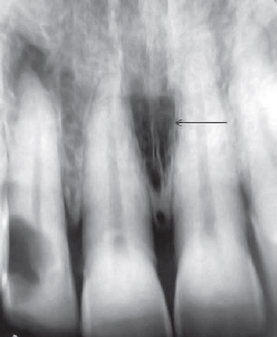

43. What is the anatomical structure indicated by arrow in this radiograph?

Maxillary Sinus The borders of the maxillary sinus appear on periapical radiographs as a thin, delicate, tenuous radiopaque line. In adults the sinuses usually extend from the distal aspect of the canine to the posterior wall of the maxilla above the tuberosity. In older adults the sinus may extend farther into the alveolar process, and in the posterior region of the maxilla its floor may appear considerably below the level of the floor of the nasal cavity. Anteriorly each sinus is restricted by the canine fossa and is usually seen to sweep superiorly, crossing the level of the floor of the nasal cavity in the premolar or canine region. Consequently, on periapical radiographs of